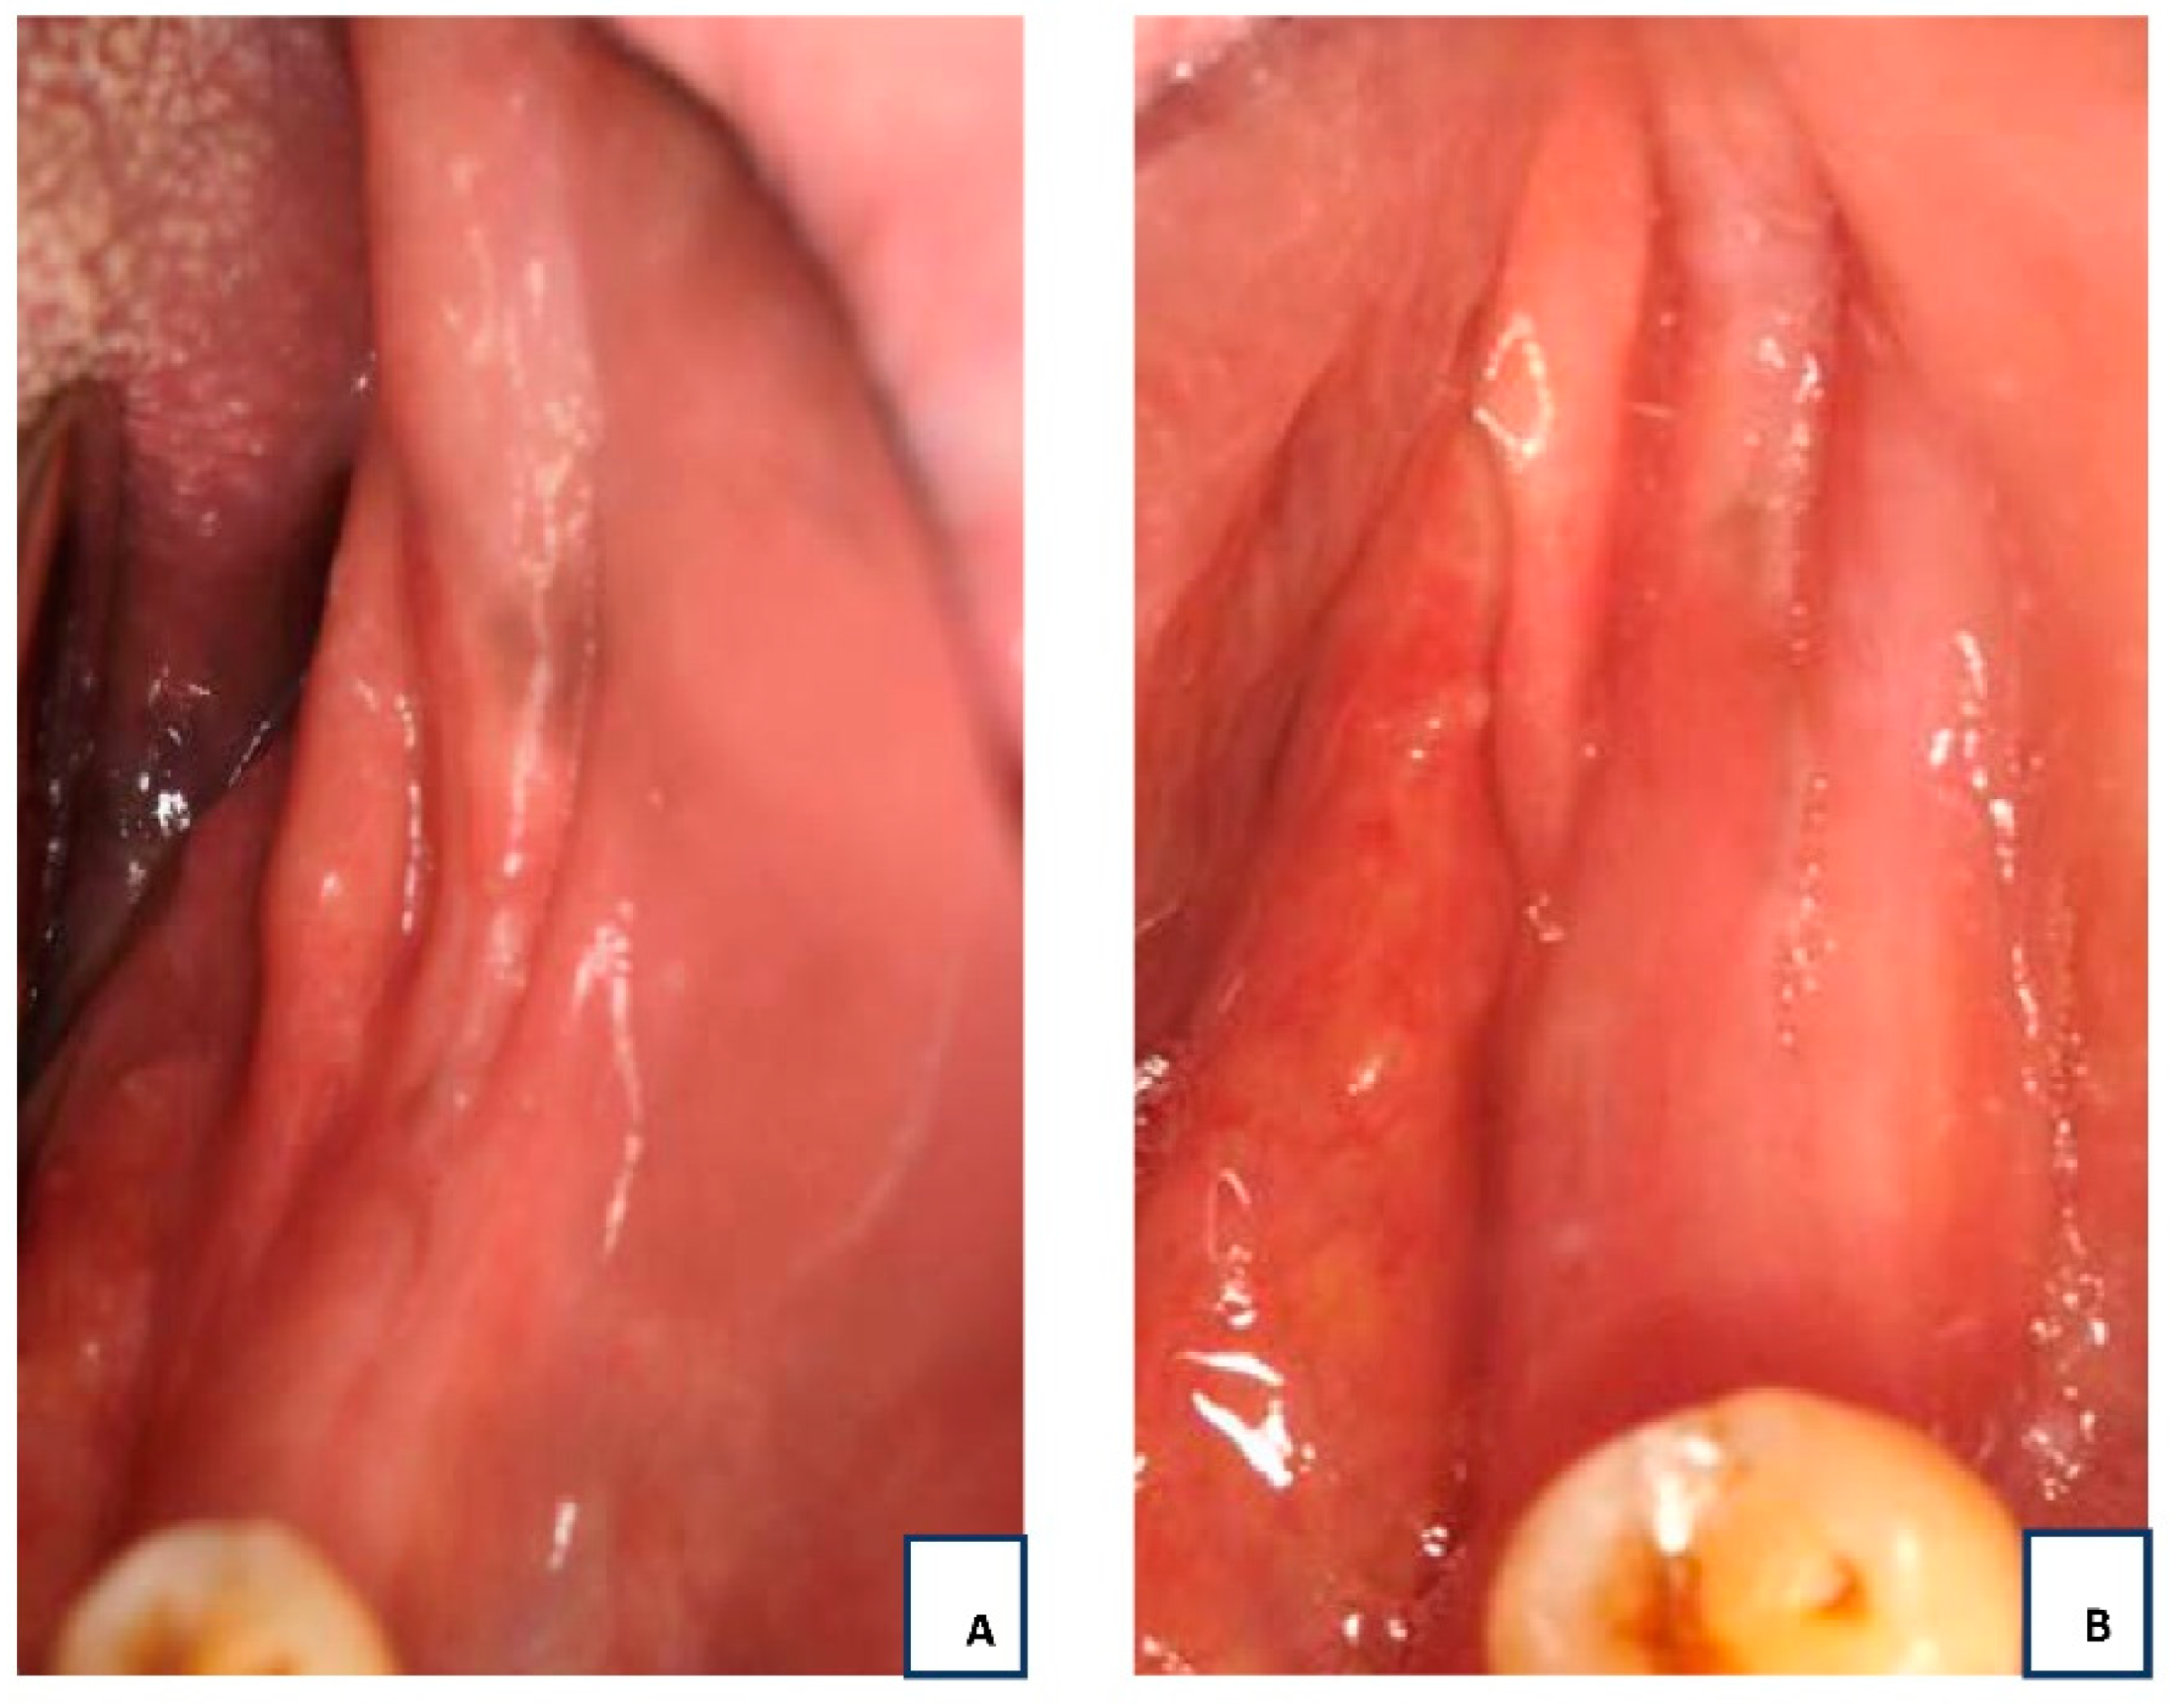

2.1. History and Clinical Examination